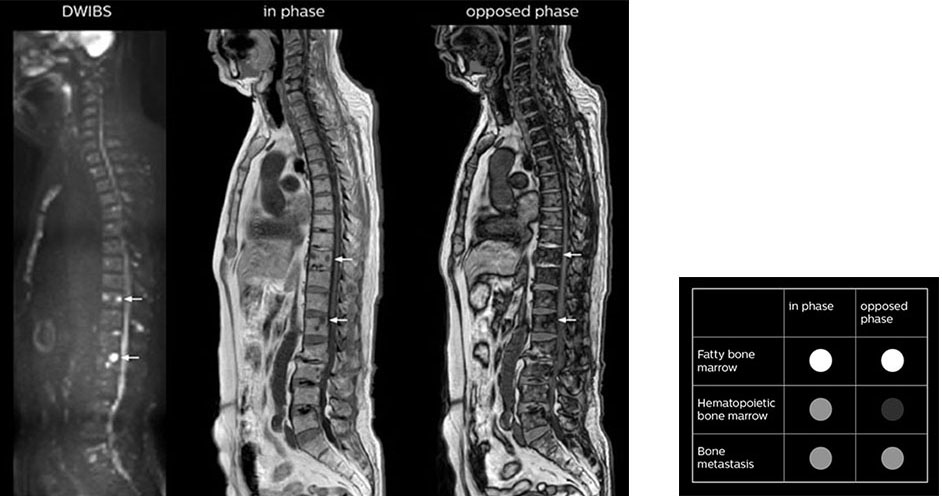

“The mDIXON fat images can help us to differentiate fatty bone marrow from bone lesions. This is especially useful in elderly people, who tend to have fattier bone marrow. The water images provide a high signal-to-noise ratio in the intestinal canal, which is valuable for visualizing lesions in the colon,” he says.

“In-phase and out-phase sagittal T1-weighted FFE images help us to visualize and further characterize bone lesions such as metastasis and bone-marrow hyperplasia that have high signal on DWI. These images are also used throughout radiotherapy, to monitor changes in the fatty bone marrow.”